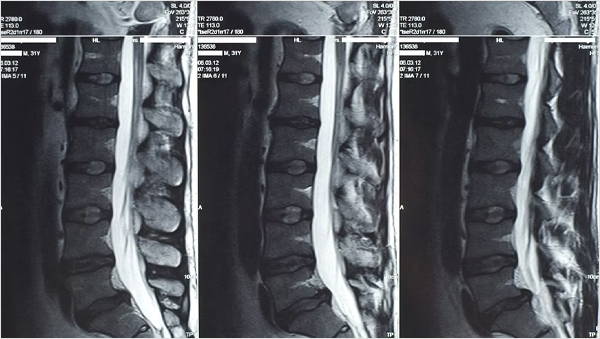

Cuando una persona que está presentando un cuadro de dolor crónico a nivel de la espalda baja se presenta a una consulta con un médico y le cuenta de su problema, lo primero que normalmente se hace es prescribir estudios de imagen (generalmente resonancias magnéticas y espinogramas). Ahora que ya conocés los datos, ya sabés que cuando un médico prescribe una resonancia magnética, las chances de que el estudio del paciente revele algún tipo de problema a nivel discal es muy grande (a mayor edad, mayor la probabilidad), pero también ya aprendiste que la probabilidad de que eso que se ve en la resonancia sea la causa de su cuadro de dolor es ínfima.